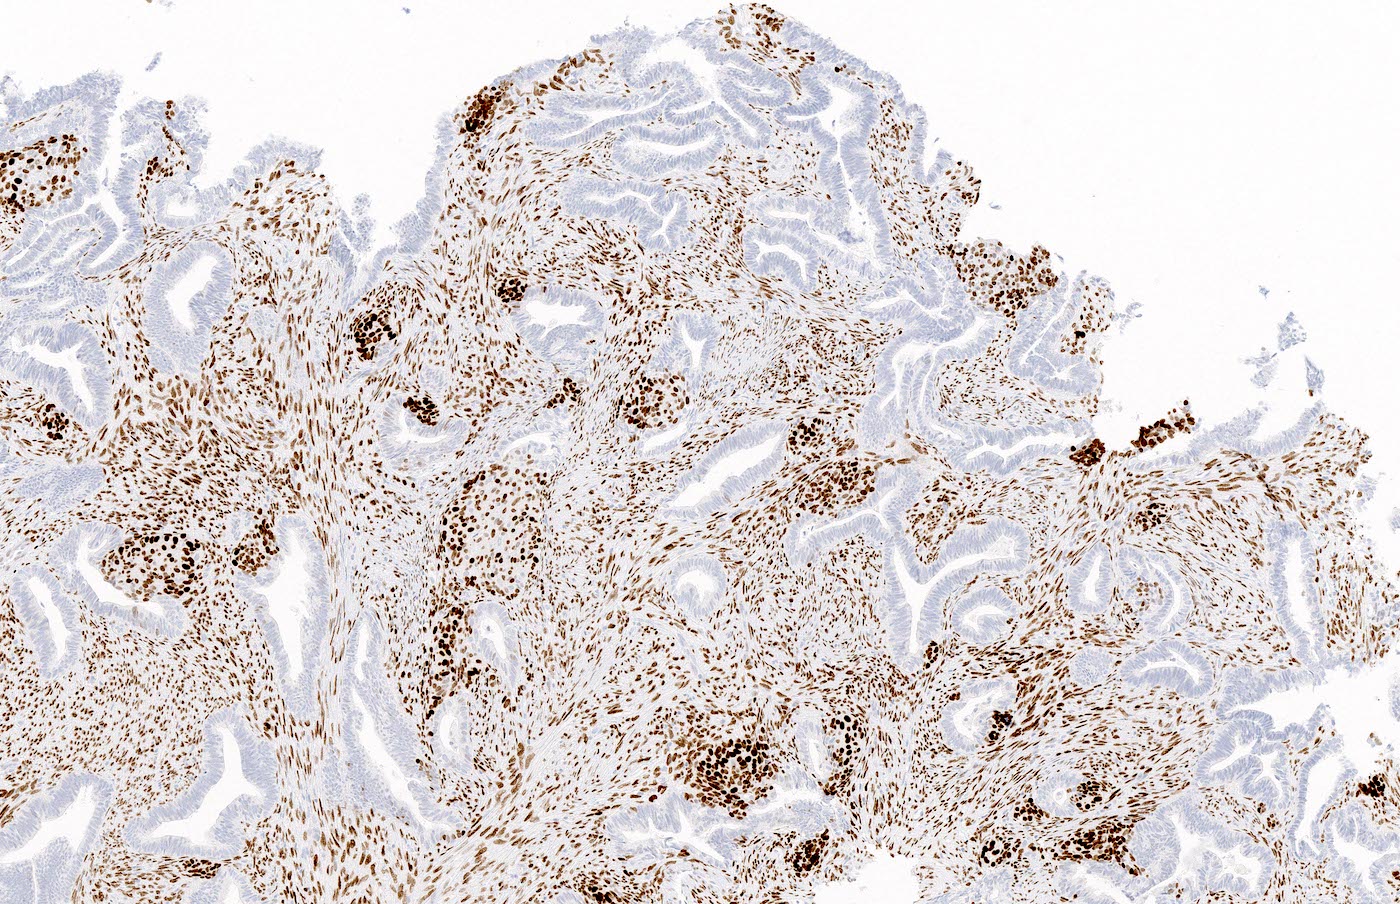

Positive stains

- Beta catenin nuclear positivity (squamous morules > glands) (Hum Pathol 2014;45:33)

- SATB2 reactivity in the stromal component (Histopathology 2021;79:96, Int J Gynecol Pathol 2019;38:397)

- Pancytokeratin, estrogen receptor and progesterone receptor typically positive in glands

- Smooth muscle actin and desmin positive in stromal muscle (Appl Immunohistochem Mol Morphol 2020;28:646)

- CDX2 and p16 positive in squamous morules (Appl Immunohistochem Mol Morphol 2020;28:646, Histopathology 2021;79:96)